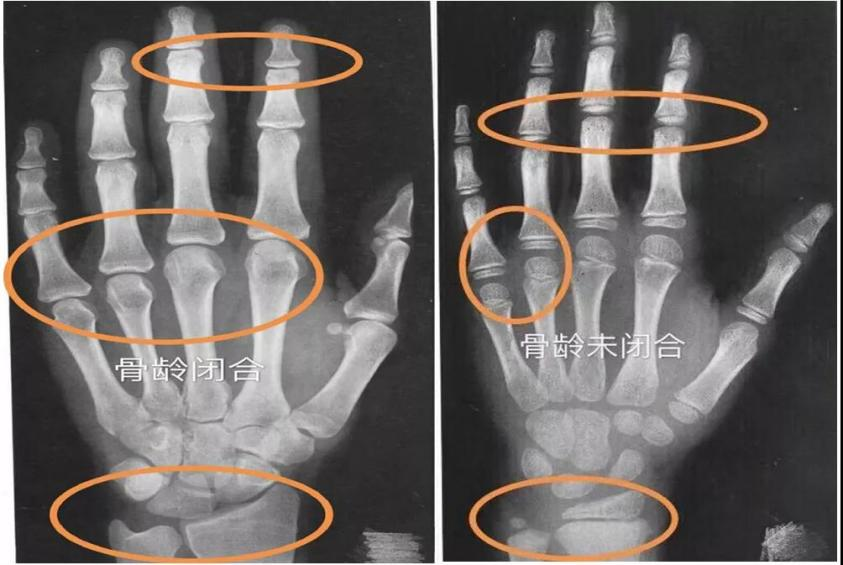

什么是骨龄?

骨龄是骨骼年龄的简称,是各年龄时的骨成熟度。通过观察骨化中心的大小、形态、结构和相互关系的变化来判断体格和生理的发育程度,通过对发育程度进行统计处理,以年龄的形式,以岁为单位进行表达的生物学年龄。正常情况下,骨龄与实际年龄的差别应在±1岁之间,落后或超前过多即为异常。

提前:骨龄比生活年龄大1岁以上;

延迟:骨龄比生活年龄小1岁以上;

正常:骨龄与生活年龄相差不超过1岁。

骨龄和身高有什么关系呢?骨龄与孩子的生长板结构存在密切关系,骨龄小代表生长潜力大,反之说明生长空间小,因此可以用骨龄来预测孩子的身高。